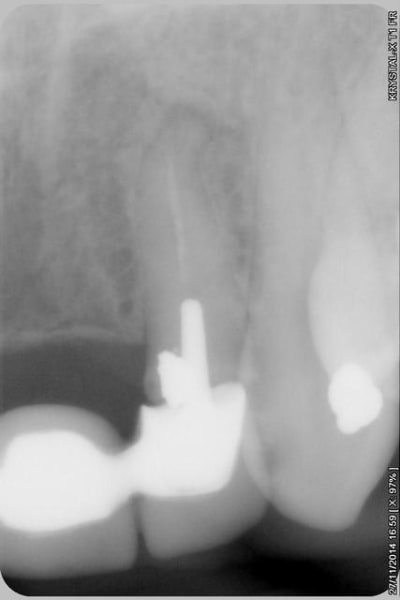

Donc dans un premier temps,je décide d'essayer de retraiter 12/22, de toute façons ça ne peut pas être pire que ce qui tiens depuis 10 ans... enfin 12 mobilité quasiment 3.

ensuite Srew post (bouh...) et résine, afin de pouvoir poser un provisoire et réfléchir à l'avenir du parodonte...car il va y avoir un problème quelle que soit la solution choisie.

Sur la reprise de 22 je pense que tu as fais un beau "tout-droit" à l'apex... le canal devait suivre la courbure.

Tu es bon pour faire une chir-apicale dans quelques mois !

je pense que le tout droit existait déjà..

oup's j'ai omis la digue...

Chir apicale si on garde la dent...

Oui oui, c'est certain ! il y avait au moins une belle butée bien engagée. Ce qui expliquerai que l'ancien traitement n'allait pas jusqu'à l'apex.

Et avec les instruments de rotation continue agressifs de reprise d'endo que l'on a maintenant, on s'engage dans la butée et on la "termine"... ça m'arrive aussi de temps en temps... de toutes façons, repasser de vieilles butées comme ça, même les endos exclusifs n'y arrivent presque jamais et font une chir apicale d'emblée.